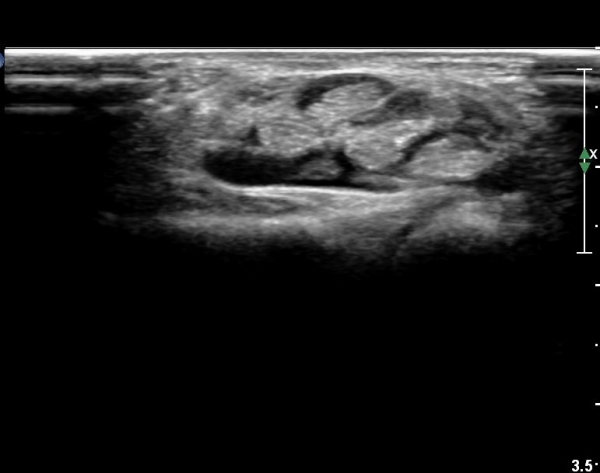

¾Æ·§ÆÈ ¸»´ÜºÎ Ⱦ´Ü¸é°Ë»ç¿¡¼­ ¼Õ°¡¶ô ±¼°î ÈûÁÙÀÇ ºñÈÄ¿Í ÈûÁÙ ½ÉºÎ¿¡ ¼ö¾×Àú·ù°¡ °üÂûµÈ´Ù(»çÁø 1).

¼Õ¸ñ°ú ¼ö±Ù°ü±ÙÀ§ºÎ Ⱦ´Ü¸é°Ë»ç¿¡¼­  ÈûÁÙÀÇ ºñÈÄ¿Í ÈûÁÙ ÁÖÀ§ Ȱ¾×¸· ºñÈİ¡ °üÂûµÇ³ª

Á¤Áß½Å°æ ºÎÁ¾Àº °üÂûµÇÁö ¾Ê´Â´Ù(»çÁø 3, 4).